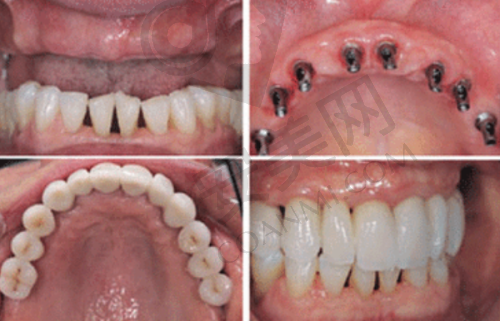

韩国neo种植牙具有诸多优势。首先,它的材料质量可靠。采用了精良的生物材料,与人体组织的相容性好,能够更好地与牙槽骨结合,提高种植的成功几率。其次,neo种植牙的设计合理,模拟了自然牙齿的形态和功能,能够修复良好的咀嚼功能。在外观上,也与自然牙齿非常相似,几乎看不出是种植牙。此外,韩国neo种植牙的研发和生产技术成熟,经过了大量的临床验证,具有较高的稳定性和耐用性。患者在使用过程中,不用担心出现松动、脱落等问题,可以长期保持良好的使用成效。

当您来到济南可恩口腔进行韩国neo种植牙时,会有一套规范的流程。首先,您需要进行全方面的口腔检查。医生会通过口腔X光片、CT等检查手段,了解您的牙槽骨密度、高度、宽度等情况,以及是否存在其他口腔疾病。然后,医生会根据检查结果,为您制定个性化的种植方案。这个方案会详细说明种植的时间、步骤、费用等信息。接下来,就是种植手术阶段。苗新海医生会在局部麻醉的情况下,将种植体植入牙槽骨内。手术过程中,医生会严格遵循无菌操作原则,确保手术的安心。术后,患者需要按照医生的嘱咐进行护理,包括服用消炎药、注意口腔卫生等。一般在种植体与牙槽骨结合稳定后,再进行牙冠的安装。整个过程可能需要几个月的时间,但在医生的专精指导下,患者可以顺利完成种植牙治疗。

许多患者在济南可恩口腔接受韩国neo种植牙治疗后,都分享了他们的真实体验。有患者表示,从就诊开始,医院的工作人员就非常热情周到,为他们提供了详细的询问和指导。在手术过程中,苗新海医生的操作非常熟练,几乎没有感觉到疼痛。术后的修复也特别顺利,按照医生的嘱咐进行护理,特别快就修复了正常的饮食。而且,种植牙的成效非常好,无论是外观还是咀嚼功能,都与自然牙齿无异。还有患者提到,医院的售后服务让他们特别放心,有任何问题都能及时得到解决。这些真实的体验表明,济南可恩口腔的韩国neo种植牙项目确实能够为患者带来良好的治疗成效。